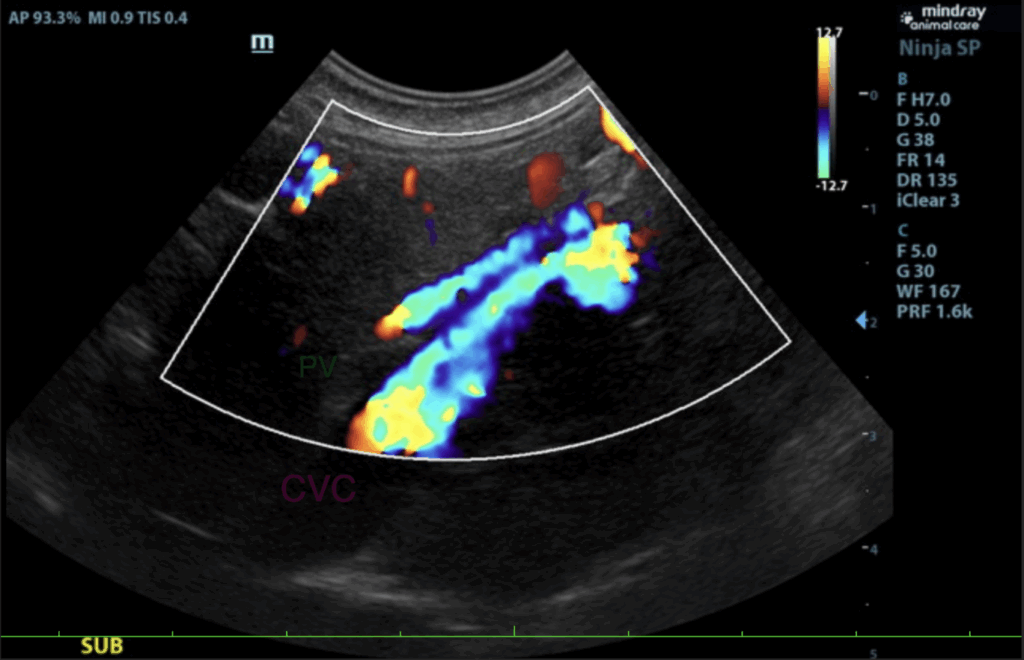

The liver was mildly subnormal in size. The hepatic parenchyma was uniform, yet hypovascular owing to the extrahepatic shunting. The extrahepatic shunt decoursed ventral caudally and then dorsally. It appeared to bypass the vena cava and aorta. It likely entered into the azygos, however, the termination

could not be found given the lack of acoustic window. The hepatic width was approximately 2.0 cm in short axis. The portal vein was subnormal in size and measured 0.34 cm after the gastroduodenal vein junction. An extrahepatic vessel was present just caudal to the pylorus and measured 1.05 cm. This is

consistent with gastric shunt. The aorta and vena cava both measured approximately 0.65 cm. The gallbladder and common bile were unremarkable.

- Extrahepatic portosystemic shunt. Gastroazygos or gastrophrenic shunt is suspected.

The Gastroduodenal vein (GDV) and splenic vein normally empty into the portal vein (PV) separately like the above image.

In this patient, the gastroduodenal vein receives the splenic vein, is enlarged and empties abnormally into the caudal vena cava.